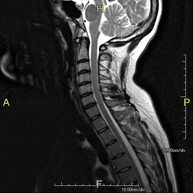

- RM de columna cervical

Prova diagnòstica no invasiva que consisteix en l'obtenció d'imatges d'alta definició anatòmica de la columna cervical mitjançant l'ús d'un camp electromagnètic i ones de ràdio (com un emissor i un receptor). No utilitza radiació ionitzant. Indicacions: traumatisme, degeneració de la columna, hèrnies. - RM de columna dorsal

Prova diagnòstica no invasiva que consisteix en l'obtenció d'imatges d'alta definició anatòmica de la columna dorsal mitjançant l'ús d'un camp electromagnètic i ones de ràdio (com un emissor i un receptor). No utilitza radiació ionitzant. Indicacions: traumatisme, problemes degeneratius, hèrnies, tumors. - RM de Columna lumbar

Prova diagnòstica no invasiva que consisteix en l'obtenció d'imatges d'alta definició anatòmica de la columna lumbar i sacre mitjançant l'ús d'un camp electromagnètic i ones de ràdio (amb un emissor i un receptor). No utilitza radiació ionitzant. Indicacions: traumatismes, ciàtica, hèrnies discals, tumors, infeccions - RM Mielografia

Prova diagnòstica no invasiva que consisteix en l'obtenció d'imatges d'alta definició anatòmica de la medul·la espinal i les arrels nervioses mitjançant l'ús d'un camp electromagnètic i ones de ràdio (amb un emissor i un receptor), així com seqüències d'estudi especials (mielogràfiques). No utilitza radiació ionitzant. Indicacions: hèrnies, compressions medul·lars. - RM de Plexe braquial

Prova diagnòstica no invasiva que consisteix en l'obtenció d'imatges d'alta definició anatòmica dels nervis que conformen el plexe del braç mitjançant l'ús d'un camp electromagnètic i ones de ràdio (amb un emissor i un receptor). No utilitza radiació ionitzant. Indicacions: estudi de la paràlisi d'extremitats superiors per a planificació quirúrgica, lesions tumorals. - RM Columna cervical + dorsal

Prova diagnòstica no invasiva que consisteix en l'obtenció d'imatges d'alta definició anatòmica de la columna cervical i dorsal mitjançant l'ús d'un camp electromagnètic i ones de ràdio (amb un emissor i un receptor). No utilitza radiació ionitzant. Indicacions: traumatisme, degeneració de la columna, hèrnies. - RM Columna dorsal + lumbar

Prova diagnòstica no invasiva que consisteix en l'obtenció d'imatges d'alta definició anatòmica de la columna dorsal i lumbar mitjançant l'ús d'un camp electromagnètic i ones de ràdio (amb un emissor i un receptor). No utilitza radiació ionitzant. Indicacions: traumatisme, degeneració de la columna, hèrnies. - RM Columna completa

Prova diagnòstica no invasiva que consisteix en l'obtenció d'imatges d'alta definició anatòmica de la columna cervical, dorsal i lumbar mitjançant l'ús d'un camp electromagnètic i ones de ràdio (amb un emissor i un receptor). No utilitza radiació ionitzant. Indicacions: detecció de metàstasi, escoliosi, traumatisme.

- RM Columna Cervical

Prova diagnòstica no invasiva que consisteix en l'obtenció d'imatges d'alta definició anatòmica de la columna cervical, mitjançant l'ús d'un camp electromagnètic i ones de ràdio (amb un emissor i un receptor). No utilitza radiació ionitzant. Indicacions: traumatisme, degeneració de la columna i hèrnies. - RM Columna Dorsal

Prova diagnòstica no invasiva que consisteix en l'obtenció d'imatges d'alta definició anatòmica de la columna dorsal, mitjançant l'ús d'un camp electromagnètic i ones de ràdio (amb un emissor i un receptor). No utilitza radiació ionitzant. Indicacions: traumatisme, problemes degeneratius, hèrnies i tumors. - RM Columna Lumbar

Prova diagnòstica no invasiva que consisteix en l'obtenció d'imatges d'alta definició anatòmica de la columna lumbar i sacre mitjançant l'ús d'un camp electromagnètic i ones de ràdio (amb un emissor i un receptor). No utilitza radiació ionitzant. Indicacions: traumatismes, ciàtica, hèrnies discals, tumors i infeccions. - RM de Sacre-còccix

Prova diagnòstica no invasiva que consisteix en l'obtenció d'imatges d'alta definició anatòmica del sacre i còccix mitjançant l'ús d'un camp electromagnètic i ones de ràdio (amb un emissor i un receptor). No utilitza radiació ionitzant. Indicacions: dolor sacrococcigi i traumatisme. - RM Columna cervical + dorsal

Prova diagnòstica no invasiva que consisteix en l'obtenció d'imatges d'alta definició anatòmica de la columna cervical i dorsal mitjançant l'ús d'un camp electromagnètic i ones de ràdio (amb un emissor i un receptor). No utilitza radiació ionitzant. Indicacions: traumatisme, degeneració de la columna i hèrnies.

- RM Columna dorsal + lumbar

Prova diagnòstica no invasiva que consisteix en l'obtenció d'imatges d'alta definició anatòmica de la columna dorsal i lumbar, mitjançant l'ús d'un camp electromagnètic i ones de ràdio (amb un emissor i un receptor). No utilitza radiació ionitzant. Indicacions: traumatisme, degeneració de la columna i hèrnies.

- RM Columna completa

Prova diagnòstica no invasiva que consisteix en l'obtenció d'imatges d'alta definició anatòmica de la columna cervical, dorsal i lumbar, mitjançant l'ús d'un camp electromagnètic i ones de ràdio (amb un emissor i un receptor). No utilitza radiació ionitzant. Indicacions: detecció de metàstasi, escoliosi i traumatisme.